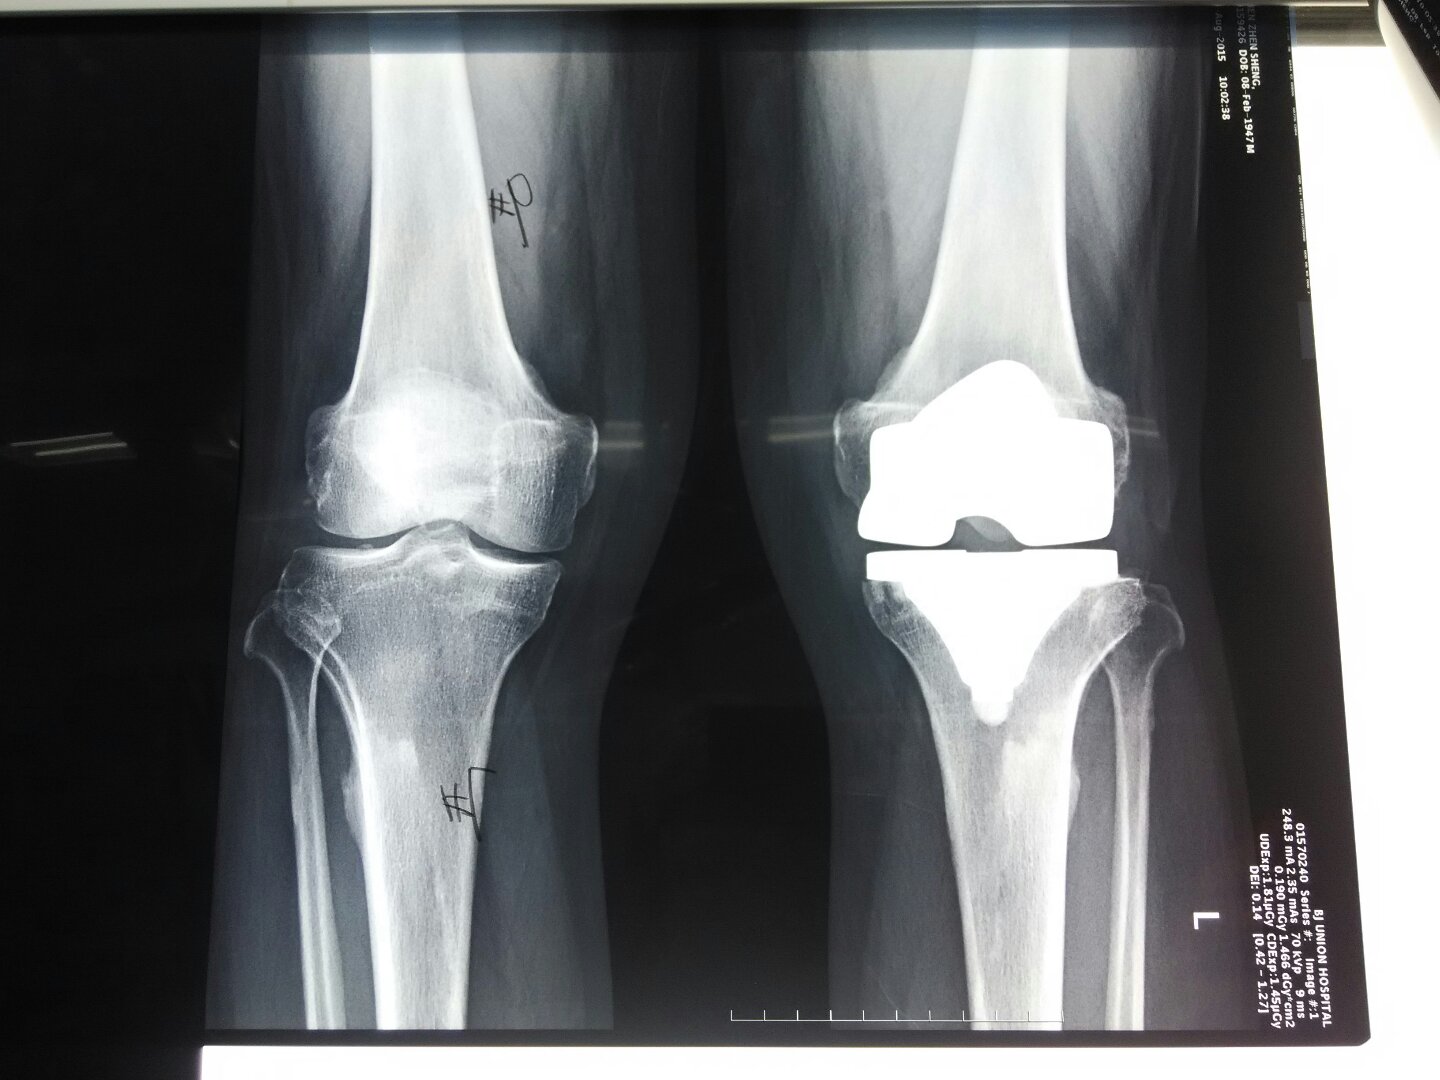

x线平片诊断的依据主要是不同机体组织对X线的吸收不同,所得图像为二维,也就是所谓的投影图像技术,不同于CT、US及MRI的断层技术。成像的缺陷是当组织有重叠时图像欠清晰。摄片的质量控制很重要,包括患者的体位及x线照射量要最佳化,以利于发现轻微的病变。对患病关节进行多角度照射检测,有助于发现关节的所有相关病变。在机体的某些部位,还要求从特殊的角度照射检查,以利于发现特别的骨折骨损伤、骨化关节间隙狭窄、骨侵蚀及囊性变。